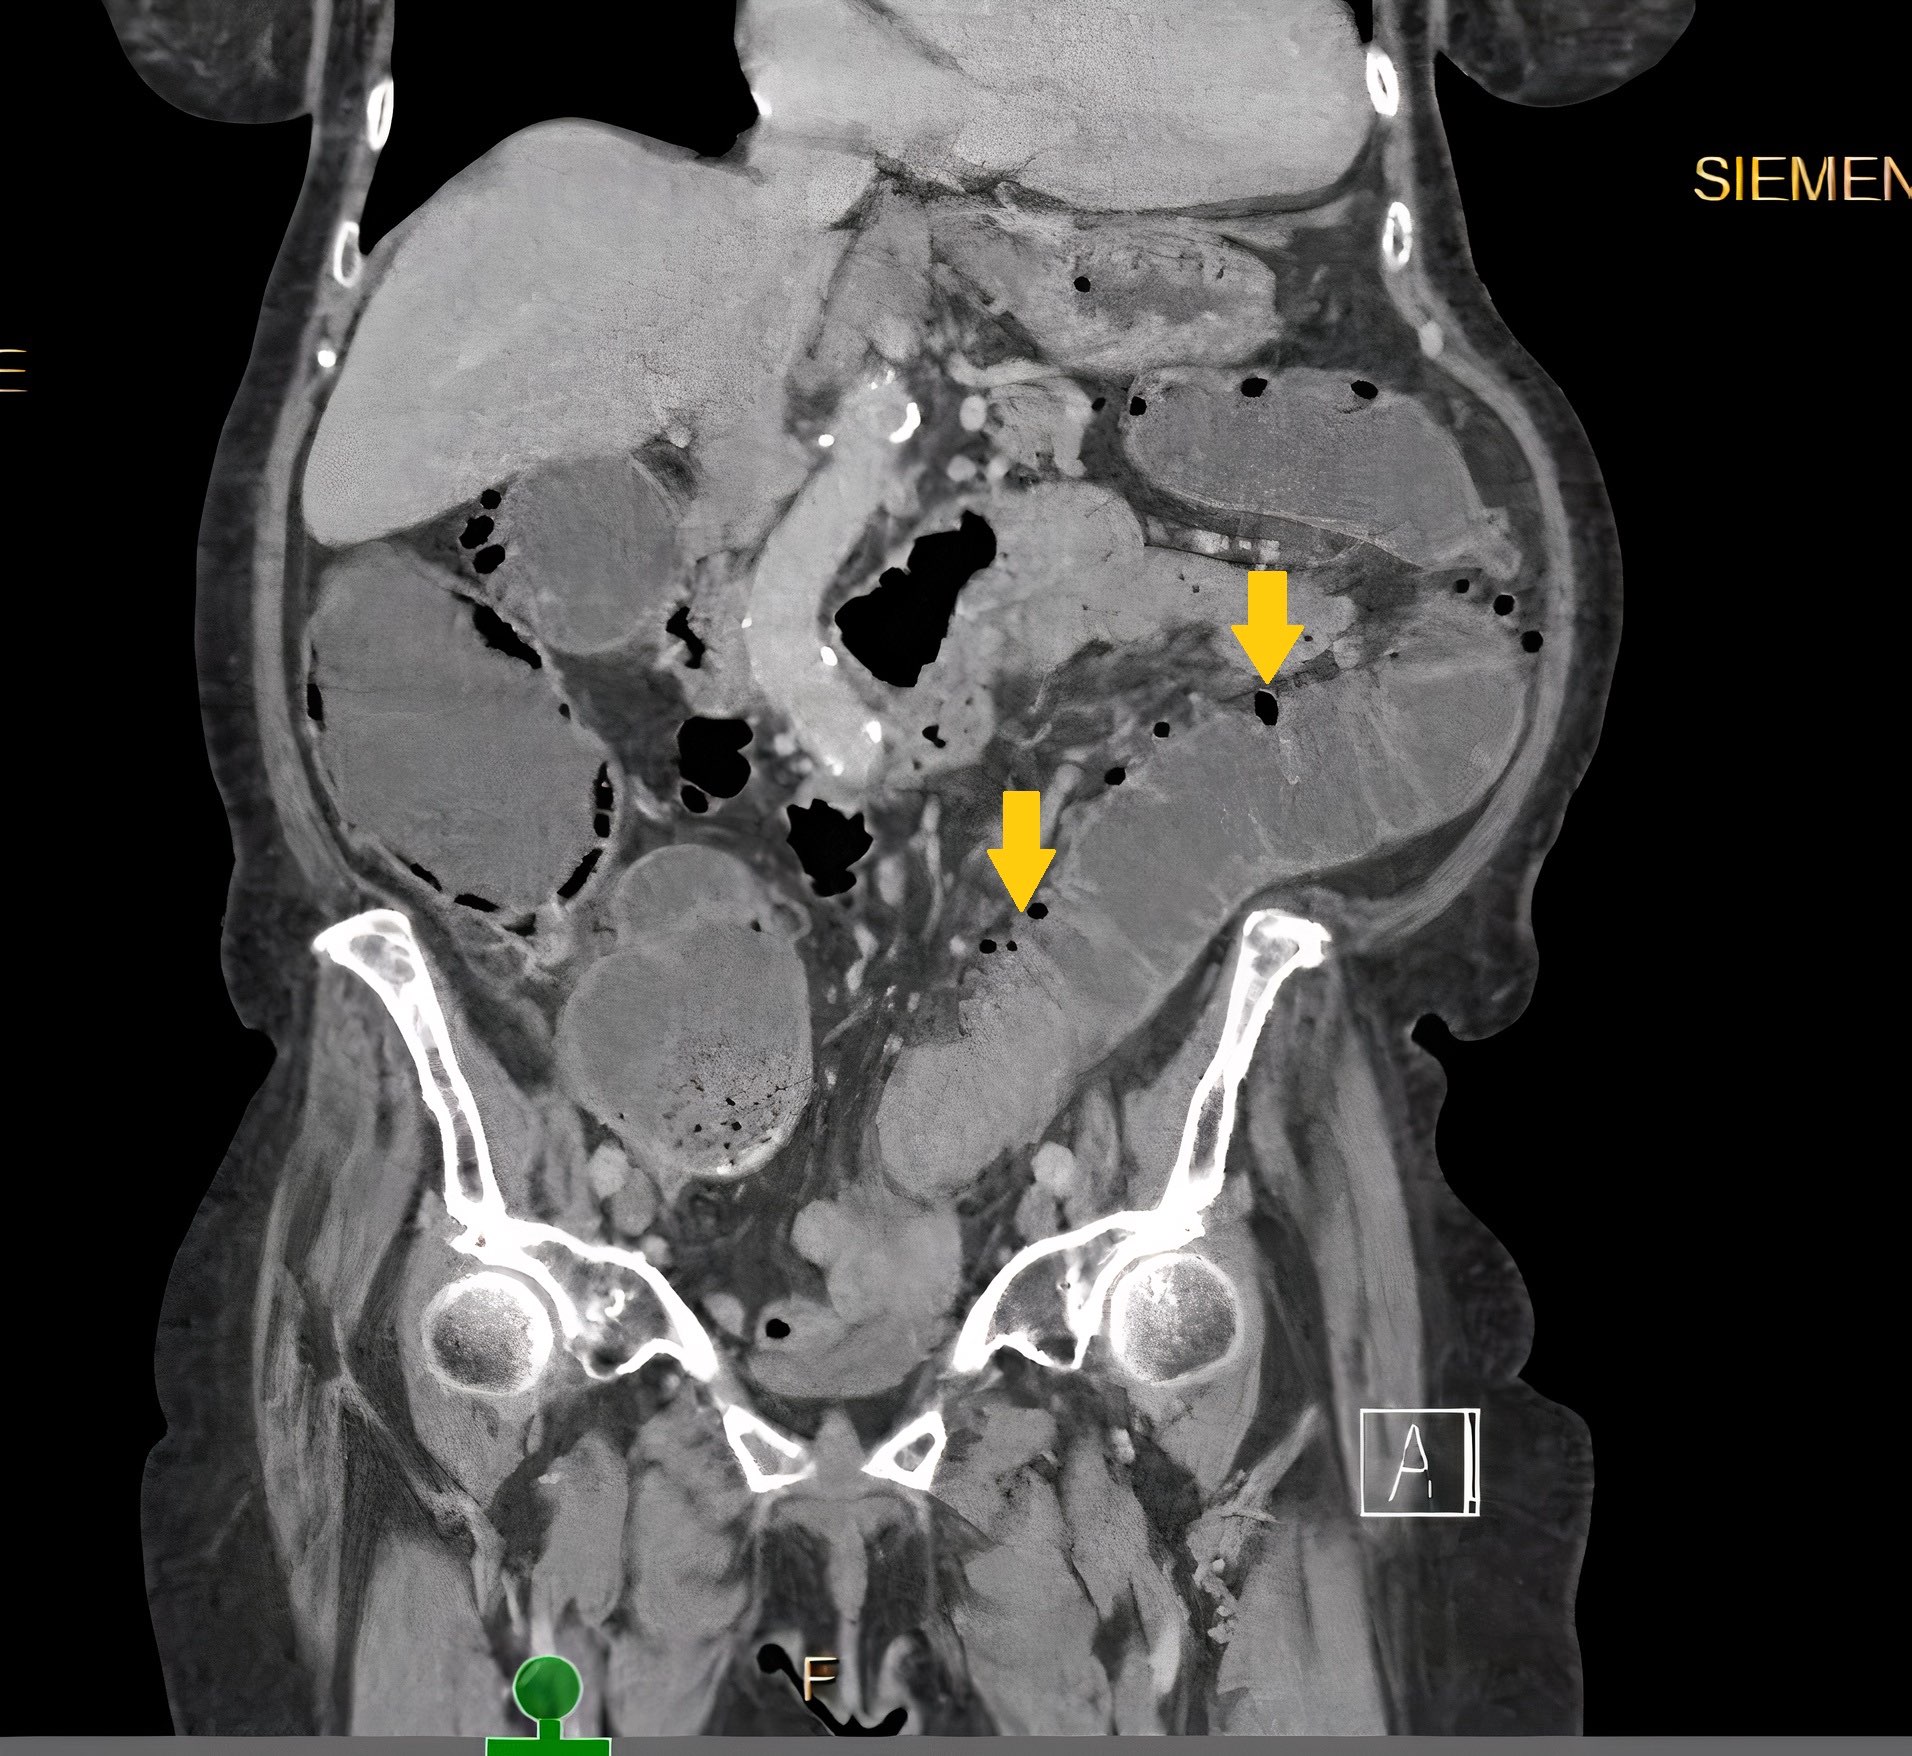

Radiology description

- Barium enema: barium filled outpouchings; can look similar to polyps

- Ultrasound: gas filled outpouchings

- CT: diverticula outlined by gas

- Intramural diverticula seen as a tiny focus of gas or contrast within the colonic wall (J Clin Gastroenterol 2004;38:S11)

- CT allows grading of severity and detection of complications (Br J Radiol 2020;93:20200670)

Radiology images